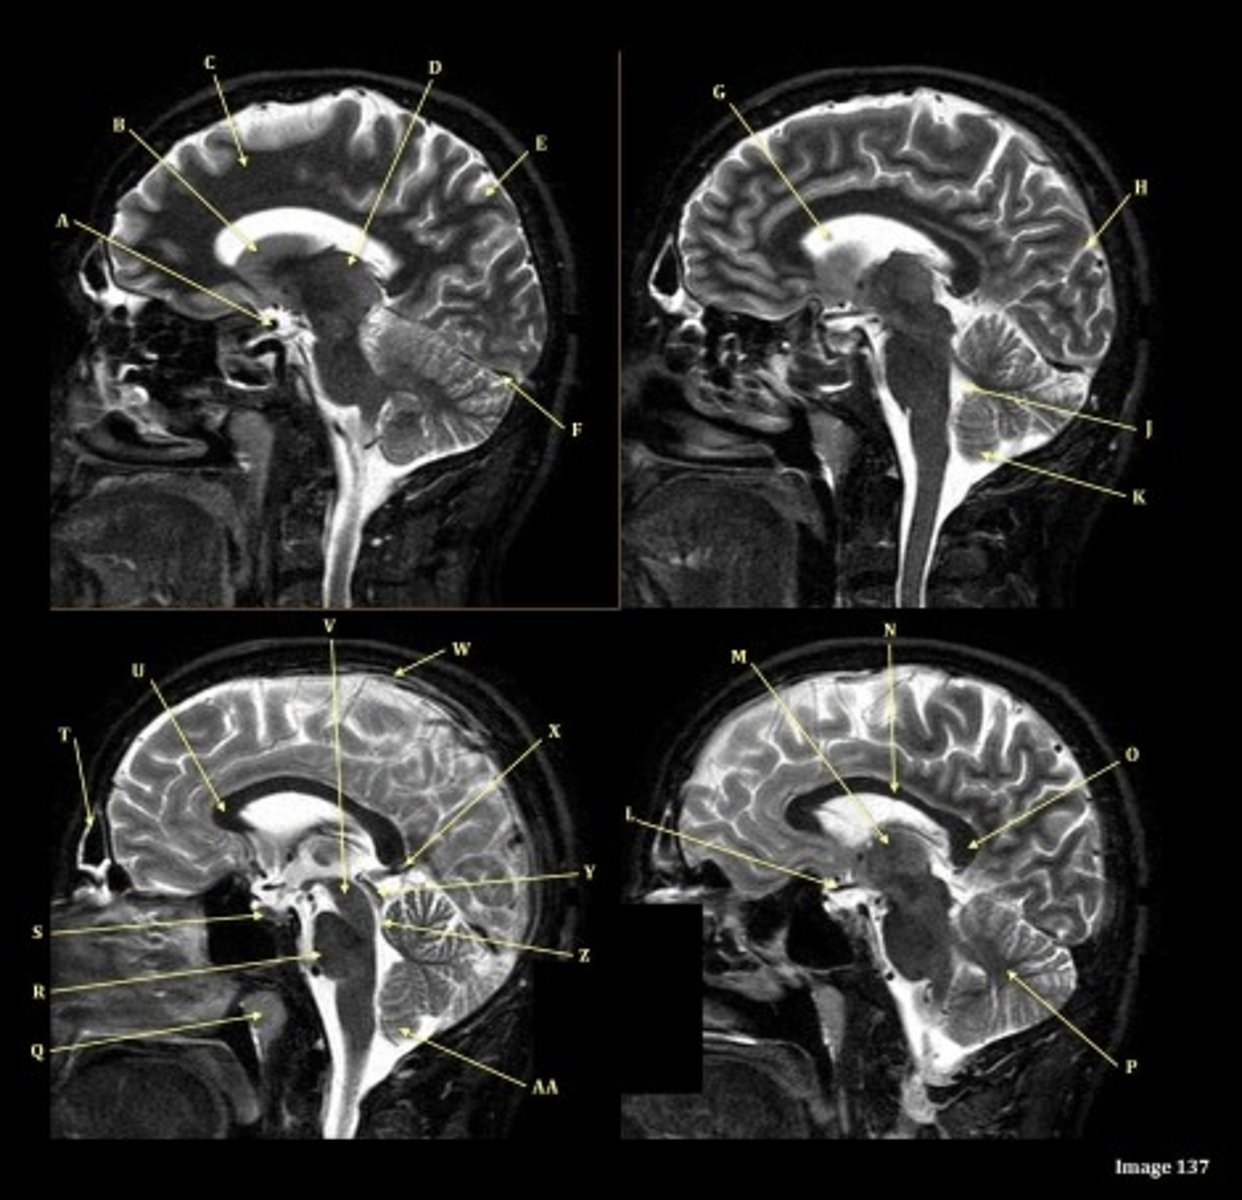

What type of sequence?

T2 FLAIR; Sagittal

A FLAIR (Fluid Attenuated Inversion Recovery) sequence is utilized to suppress signal from cerebrospinal fluid (CSF).

A

lateral ventricle

B

corpus callosum

C

thalamus

D- separates what

tentorium cerebelli- cerebrum (occipital and temporal lobes) from brainstem and cerebellum

E

fourth ventricle

F

medulla oblongata

caudate nucleus

third ventricle

D

lentiform nucleus

frontal sinus

Letter N in Image 137 is pointing to what type of tissue?

White matter

The corpus callosum is the only white matter tissue structure found in the midline sagittal slice of the brain.